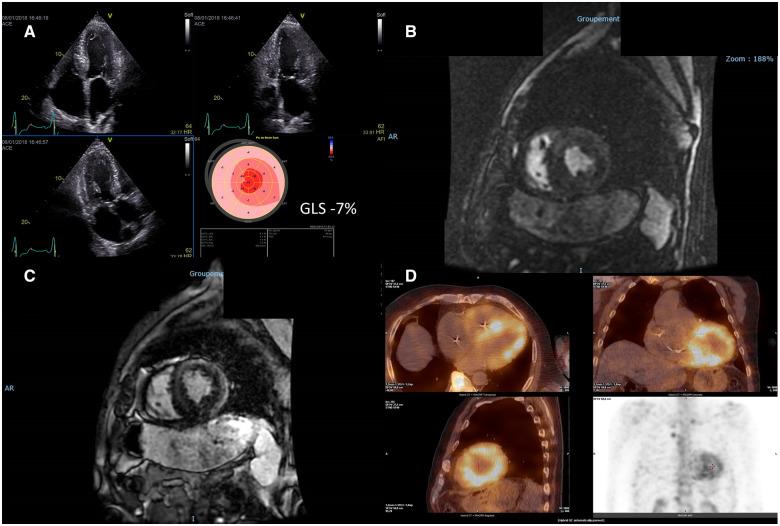

We report two cases of patients with transthyretin amyloidosis (ATTR) who developed heart failure and depressed left ventricular ejection fraction (LVEF) following permanent right ventricular (RV) pacing but highly responded to cardiac resynchronization therapy (CRT).

我们报告两例转甲状腺素蛋白淀粉样变性(ATTR)患者,在永久性右心室(RV)起搏后发生心力衰竭且左心室射血分数(LVEF)降低,但对心脏再同步治疗(CRT)反应良好。

The impact of RV pacing and CRT in cardiac amyloidosis is not known. In our cases, the detrimental effect of permanent RV pacing on left ventricular (LV) systolic function and heart failure symptoms was suggested by both permanent RV pacing mediated functional and LV function decline and LV systolic dysfunction reversal following CRT along with QRS width reduction. Whether cardiac resynchronization should be readily recommended in ATTR patients who need ventricular pacing whatever the LVEF deserves further investigation.

RV起搏和CRT对心脏淀粉样变性的影响尚不清楚。在我们的病例中,永久性RV起搏介导的功能和左心室功能下降以及CRT后左心室收缩功能障碍逆转伴QRS波宽度减小提示永久性RV起搏对左心室(LV)收缩功能和心力衰竭症状有不良影响。对于无论LVEF如何都需要心室起搏的ATTR患者是否应立即推荐心脏再同步治疗值得进一步研究。